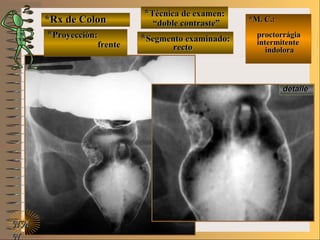

*Rx de Estómago*Rx de Estómago

**Proyección:Proyección:

**Técnica de examen:Técnica de examen:

A-A-

B-B-

C-C-